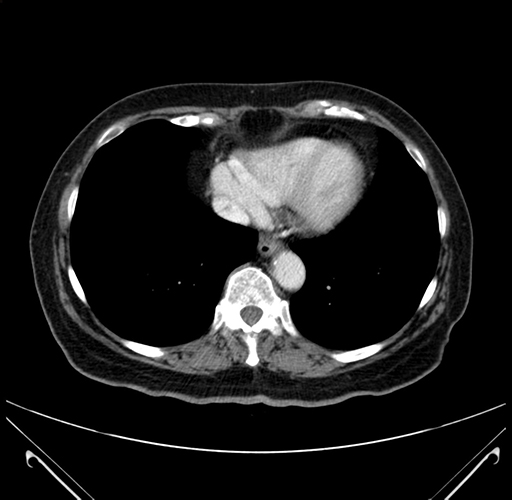

Pre-Chemo: Axial Venous